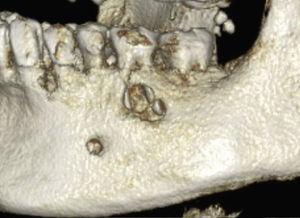

En la ortopantomografía de este paciente se observa una zona hipodensa localizada (aclaramiento) perirradicular en el diente 36 (fig. 1). La estructura mencionada abarca desde el ápice mesial del diente 37 hasta el ápice del diente 35. En la tomografía volumétrica dental adquirida consecutivamente, la masa hipodensa ocupante del espacio se extiende hacia caudal hasta el conducto mandibular del lado izquierdo y hacia bucal hasta el hueso compacto bucal (figs. 2 y 3). Este presenta dos perforaciones ovales a la altura del diente 36 (fig. 4). El techo del conducto mandibular del lado izquierdo no es apreciable en un tramo de aproximadamente 7mm. Se observan íntegramente las raíces de los dientes 35, 36 y 37.

Debido a las dimensiones del proceso y a la presencia de perforación del hueso compacto bucal, además de un quiste se sospechó como diagnóstico diferencial la presencia de un granuloma eosinófilo. En la preparación histológica de la muestra obtenida por resección pudo confirmarse un quiste radicular.